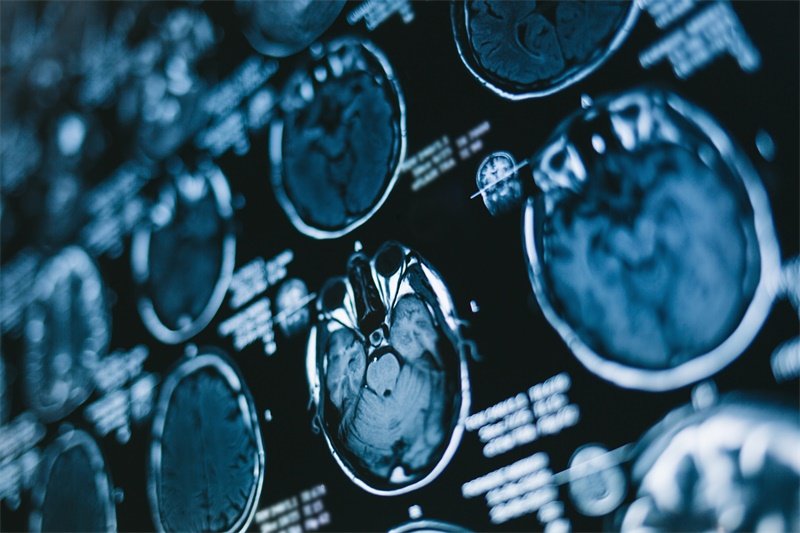

"左脑脉络丛占位边界清"是影像学检查(如CT/MRI)中对左侧脑室内脉络丛区域异常病变的描述,指该占位性病变与周围正常脑组织分界清晰,通常提示肿瘤可能为良性或生长较局限。脉络丛是脑室内分泌脑脊液的结构,此处占位常见脉络丛乳头状瘤(WHOⅠ级,儿童多见)或脉络丛囊肿(成人偶发),少数为转移瘤。边界清晰的特征在影像上表现为病变边缘光滑锐利,无"毛刺"或浸润性生长表现,增强扫描多呈均匀强化,周围脑组织无水肿带。这类占位可能引起脑脊液循环障碍(如头痛、呕吐等脑积水症状)或局部压迫症状(如肢体无力、癫痫),但进展相对缓慢。诊断需结合年龄、病史及肿瘤标志物(如GFAP、S-100),最终确诊依赖病理活检。治疗上,无症状小囊肿可观察;有症状或肿瘤倾向者建议手术切除,因边界清晰且多位于脑室内,全切成功率较高,术后需监测脑脊液分泌平衡。总体预后良好,但需定期复查MRI以防复发,尤其是儿童患者术后可能需脑脊液分流术辅助。

影像学检查是诊断脉络丛占位病变的核心技术,通常包括:

1. CT扫描:可以帮助医生观察到脉络丛及邻近结构的情况,判断病变的体积与性质。

2. MRI检查:磁共振成像提供了更为详细的软组织对比,适用于分析脉络丛内病变的性质。